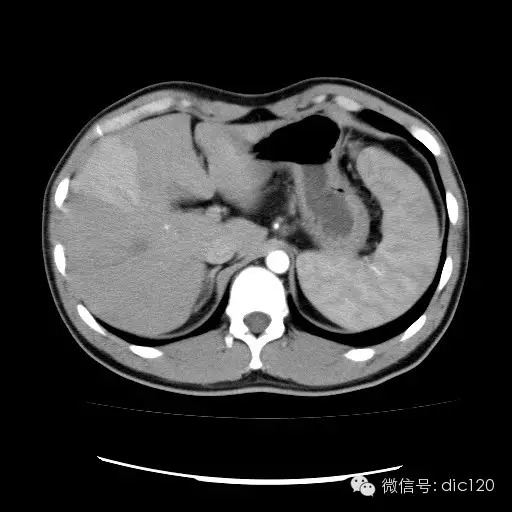

| 影像表现及分析: | 影像表现:动脉期扫描肝右叶紧贴边缘见一过性楔形高密度强化区,边界清,边缘平直,临近血管走形自然,门静脉期期恢复正常肝实质密度,延迟保持与肝实质密度一致。 |

| 疾病总结: | 正常肝脏的双重血供并非2个独立系统,两者之间有许多交通吻合,包括①肝窦间通路.②脉管间途径.③血管丛途径,即胆管周围血管丛途径.当肝脏发生血供障碍时,通过神经一体液因素的调节这些交通吻合支开放,双重供血发生血流量的变化甚至血流方向的改变.肝脏的这种”一过性”灌注异常在SCT表现为肝动脉期一过性肝实质强化(THPE).一过性肝实质强化差异是SCT增强扫描于肝动脉期表现的肝脏一过性灌注异常,大多数情况下它反映了局部肝脏双重血供的重新分布,即局部肝实质门静脉或肝静脉血流量减少,肝动脉血流量增多或为肝动脉门静脉分流或局部肝脏的变异或迷走血供所致。典型CT表现为肝动脉期一过性楔形或三角形高密度强化区,边缘平直,常位于肝脏边缘部位,其中血管走行正常,门静脉期恢复为正常肝实质密度。放射学医师应加强对一过性肝实质强化CT表现的认识。 |